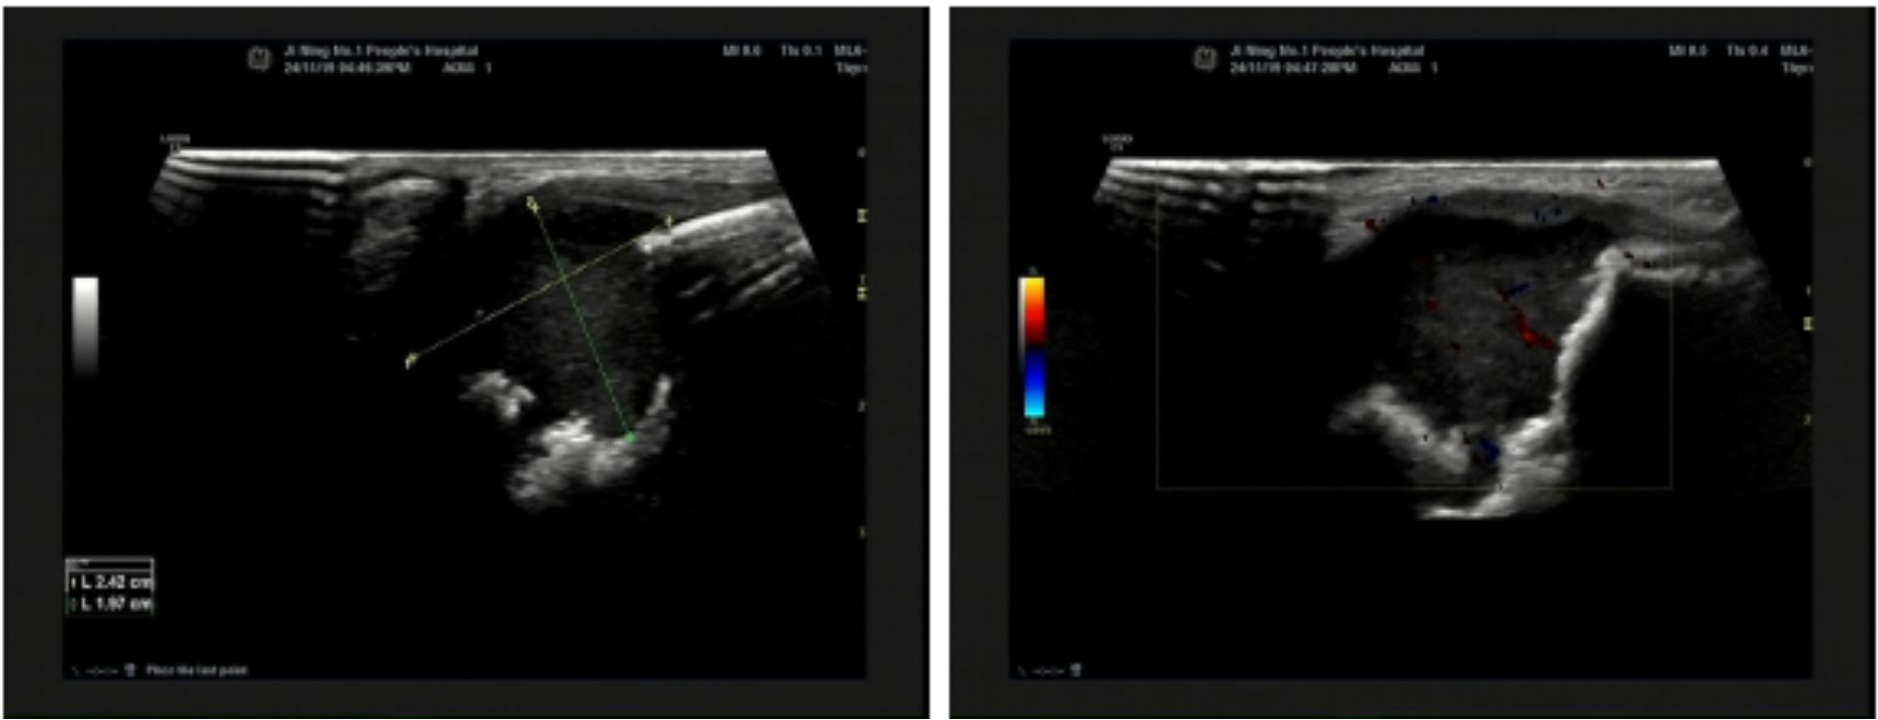

辅助检查:1) 血白细胞(WBC) 15.42 × 109/L ↑ (4.8~14.6 × 109),淋巴细胞(LYM#) 9.72 × 109/L ↑ (2.5~9 × 109),C反应蛋白(CRP1) 45.05 mg/L ↑ (0~10)。2) 体表包块彩超(图1)示:左耳后所述处下方可见范围约为2.4 × 1.8 × 2.0 cm低至无回声区,边界清,回声不均,内见密集点状回声,CDFI:其内及周边可见血流信号。3) 硬性耳内镜检查(图2)示:左侧外耳道充血肿胀,外耳道见白色分泌物,鼓膜窥不到;右外耳道通畅,稍充血,见少许分泌物,鼓膜完整。4) 颞骨CT (图3)示:左侧颞骨乳突部骨质破坏,左侧乳突气房显示欠清,局部见团块状软组织密度灶,密度欠均,边界欠清,较大截面约2.3 cm × 1.8 cm,CT值约为33~45 HU:左侧耳后软组织稍肿胀,左侧外耳道壁增厚,左侧鼓膜增厚。右侧外耳道未见明显异常。右侧乳突气房气化可。双侧中耳鼓室、右侧乳突窦腔清晰,腔内未见明显异常高低密度影。双侧听小骨未见明显异常。双侧内耳和内听道未见明显异常。

Figure 3. The left mastoid portion of the temporal bone shows osteolytic destruction. The aeration of the left mastoid air cells is obscured, with a visualized localized, ill-defined soft-tissue density mass showing heterogeneous density. The larger cross-sectional area measures approximately 2.3 cm × 1.8 cm, with CT values ranging from approximately 33 to 45 Hounsfield Units (HU). There is mild soft-tissue swelling posterior to the left ear. The wall of the left external auditory canal and the left tympanic membrane are thickened. The right external auditory canal shows no significant abnormalities. The right mastoid air cells are well-pneumatized. The bilateral middle ear tympanic cavities and the right mastoid antrum are clear, with no significant abnormal high- or low-density opacities observed within these spaces. The bilateral ossicular chains show no significant abnormalities. The bilateral inner ear structures and internal auditory canals show no significant abnormalities

3. 左侧颞骨乳突部骨质破坏,左侧乳突气房显示欠清,局部见团块状软组织密度灶,密度欠均,边界欠清,较大截面约2.3 cm × 1.8 cm,CT值约为33~45 HU:左侧耳后软组织稍肿胀,左侧外耳道壁增厚,左侧鼓膜增厚。右侧外耳道未见明显异常。右侧乳突气房气化可。双侧中耳鼓室、右侧乳突窦腔清晰,腔内未见明显异常高低密度影。双侧听小骨未见明显异常。双侧内耳和内听道未见明显异常